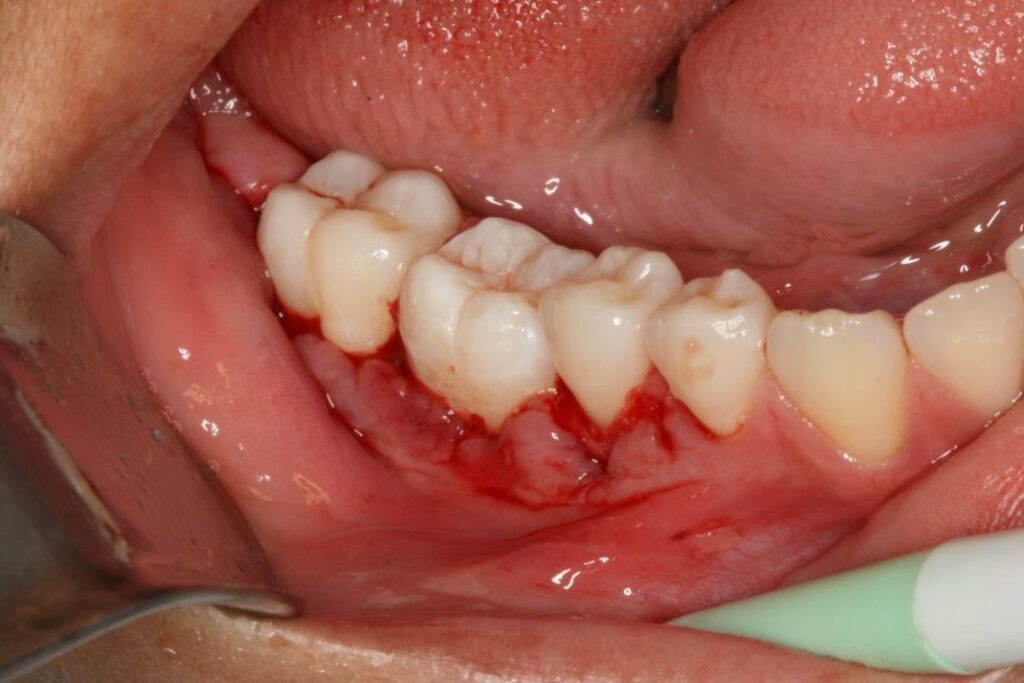

Desgastes nas proximais da coroa do dente transplantado foram necessárias para melhor adaptação do dente no novo posicionamento na arcada dentária (figura 6 e 7).

Figura 6 – desgaste nas proximais da coroa do elemento transplantado

Figura 7 – Dente posicionado no alvéolo dentário

Após sutura do tecido foi feito contenção semi-rígida com fio ortodôntico n° 0 para fixação do elemento dentário no alvéolo, posicionado elemento transplantado abaixo da linha de oclusão para evitar traumas oclusais (figura 8 e 9).